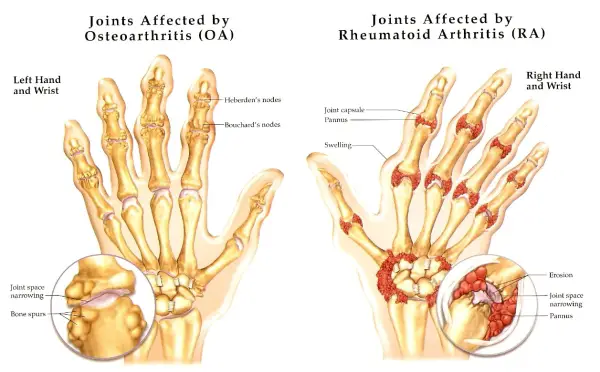

Симптомы и лечение остеоартроза узелков Гебердена: фотогалерея